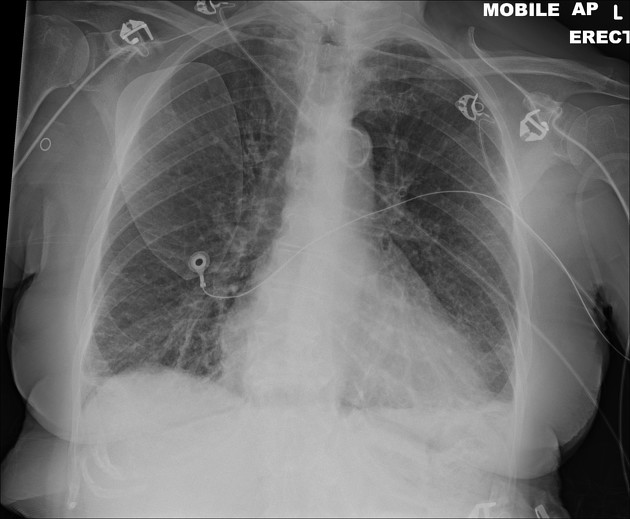

Describe the abnormality demonstrated on this supine CXR.

Right-sided deep sulcus sign and loss of lung markings ipsilaterally (collapse) indicate a right-sided pneumothorax. An ICC can be seen over the right lung.